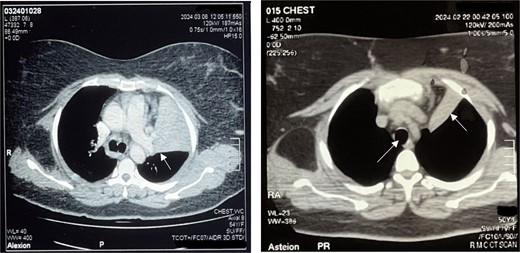

Bronchoscopy confirmed complete occlusion of the left upper lobe and lingula by a mass (Fig. 2), and subsequent CT with contrast revealed luminal obliteration of the left upper lobe bronchus by a long linear fat-density structure. A right posterolateral chest wall lipoma was also noted. Bronchoalveolar lavage at our center showed bronchial mucosa with moderate lymphoplasmacytic infiltrates, with fungal culture positive for Aspergillus terreus and bacterial culture positive for Staphylococcus aureus. GeneXpert testing excluded tuberculosis.

Bronchoscopy report confirming a mass completely occluding the left upper lobe and lingula (Fig. 3). Endobronchial lipoma along the left main bronchus (white arrowhead).

The patient underwent left-sided thoracotomy and upper lobectomy due to severe parenchymal inflammation and necrosis of the left upper lobe, with histopathology confirming a well-circumscribed adipocytic lesion consistent with lipoma measuring ~9.1 × 6.9 × 9.3 mm in the bronchus (Figs 3 and 4). Adjacent lung tissue exhibited organizing pneumonia and bronchiectasis. Post-operatively, she recovered well and was discharged home in stable condition on the fourth day.